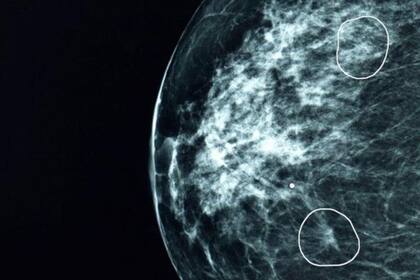

Una herramienta de inteligencia de artificial (IA) que se está probando en el hospitales británicos logró identificar pequeños signos de cáncer de seno en 11 mujeres que habían pasado desapercibidos a la revisión de los médicos.

La herramienta, llamada Mia, se probó en varios centros de salud de Reino Unido y analizó cerca de 10.000 mamografías.

La mayoría de ellas no mostraban signos de cáncer, pero la herramienta logró de manera exitosa identificar las que sí los presentaban, incluyendo las de 11 pacientes que no habían sido diagnosticadas por los médicos.

En sus etapas iniciales, los cánceres pueden ser extremadamente pequeños y difíciles de identificar.

La BBC pudo ver la herramienta en acción en el hospital Grampian, presenciando cómo unos tumores prácticamente invisibles al ojo humano eran señalados por la herramienta. Esos tumores, dependiendo de su composición, pueden crecer y esparcirse de forma muy rápida.